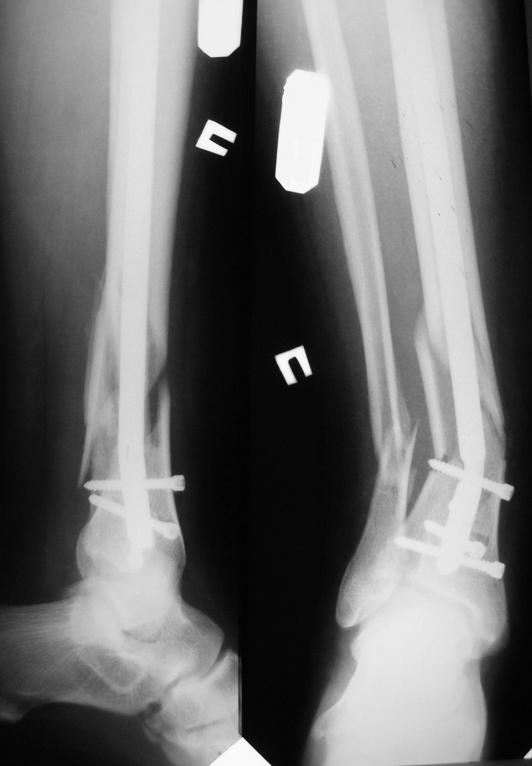

Уважаемые коллеги! Больной 36 лет, Ds: оскоьчатый перелом костей правой голени в н/3 со смещением. 3.02.09. выполнен интрамедуллярный блокирующий остеосинтез б/берцовой кости титановым стержнем диамерт 10 мм. 9.02.09. больбной упал в палате, загнул стержень. Помогите советом!

Мне кажется, что стержень сломан, а не согнут. Если присмотреться - то видна ступенька в миллиметр.

Наверно, он его сломал, а не согнул. Как это у него так получилось упасть, интересно.

Надо бы удалить да пересинтезировать стержнем большего диаметра.

Это хорошый пример стабильности фиксации при коротких дистальных отломках.

Согнул или сломал можно определить по подвижности.

Сейчас в отделении лежит пациент с похожим переломом. Изначально было принято решение об установке штифта. Однако, обсуждая случай на конференции, коллеги старой закалки напомнили, что данный вариант перелома - является нестабильным. Таким образом вальгусная деформация при нагрузки - законное осложнение. Т.е....советы коллег просто об усилении штифта - не совсем корректное. Необходимо фиксировать, помимо б/берцовой кости, и малоберцовую ( например 1/3 трубчатой пластиной).

такого рода хлипких тонких стержней. Если взять стержень помощнее, диаметром мм 12, да запереть его не двумя, а тремя винтами, да диаметром не 4,5, а 6 мм, то подобных проблем не встречается даже при немедленной полной нагрузке.